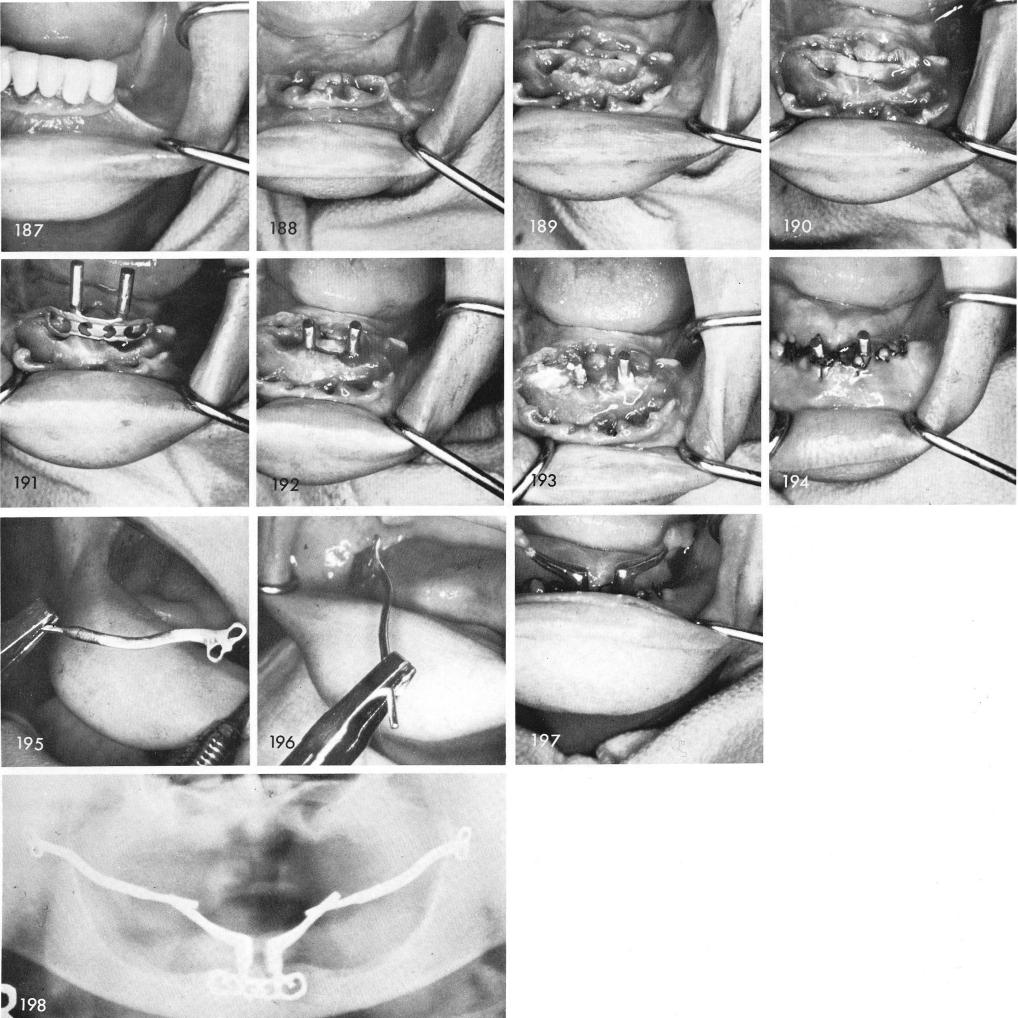

The next case shows periodontally involved anterior teeth that were removed, figs. 187, 188, the sockets cleansed of all debris, fig. 189, the groove made, fig. 190, and the blade inserted, figs. 191, 192. Sterile plaster of Paris was gently moulded into the open socket areas, fig. 193, and the tissues were sutured closed, fig. 194. Because of the difficulty in casting the long hollow tubes, I developed a five piece system using solid arms posteriorly and a shorter hollow tube anteriorly, extending from each anterior coping, figs. 195, 196. Due to a miscast of the anterior hollow extension tubes at the last moment I afixed the posterior solid arms to the original anterior solid arms with Duralay for 24 hours, figs. 197, 198, until the hollow anterior extensions were

1 Extraction of periodontally involved mandibular anterior teeth